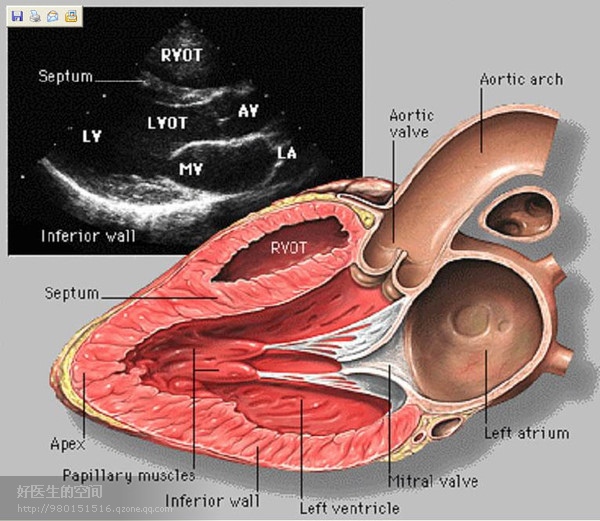

经典心脏超声切面图及解剖标示